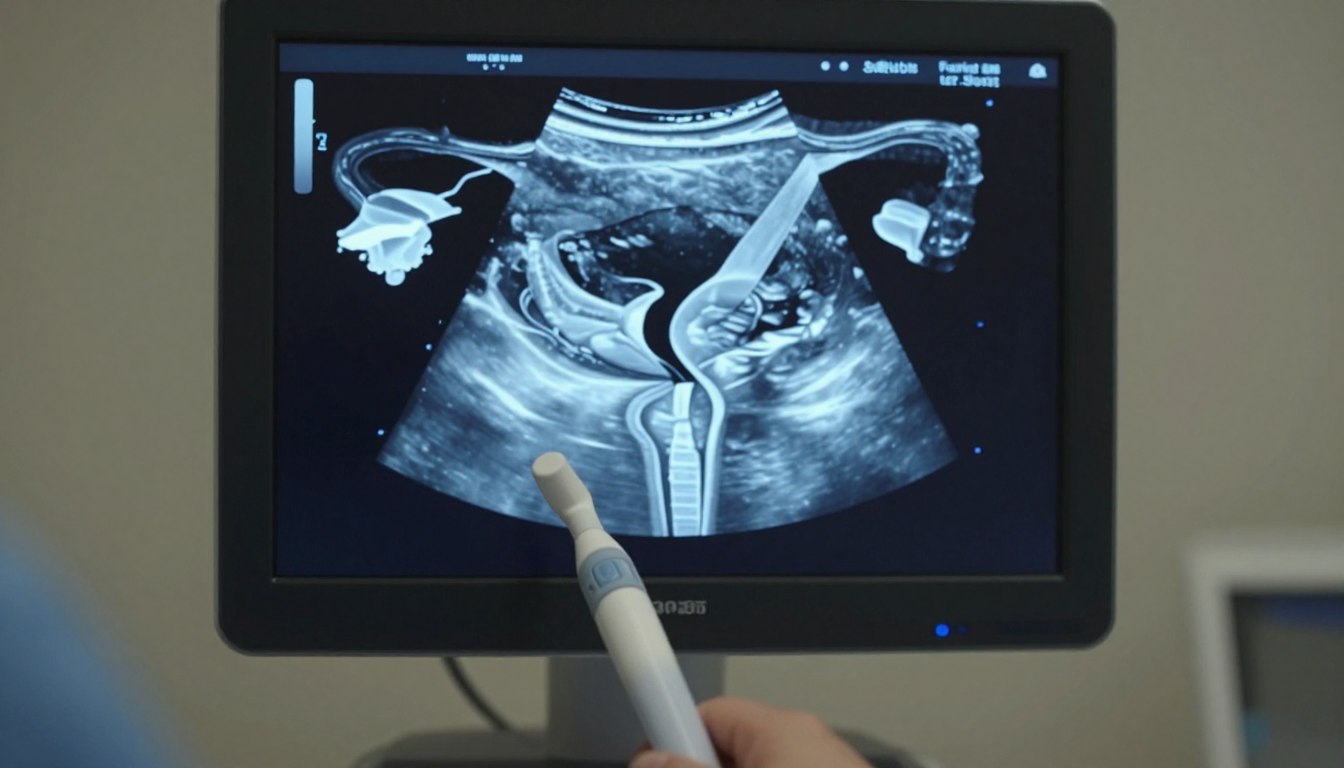

Czy nietypowy kształt narządu rodnego może ukrywać przyczynę problemów z donoszeniem ciąży? Takie pytanie często stawiają pary i lekarze, gdy pojawiają się nawracające poronienia lub…